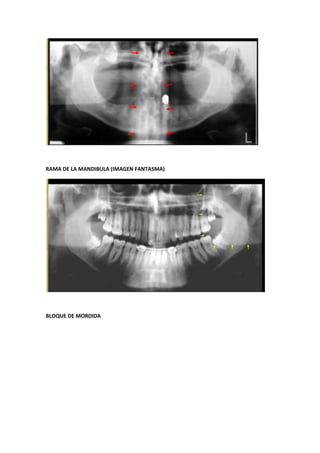

RAMA DE LA MANDIBULA (IMAGEN FANTASMA)

BLOQUE DE MORDIDA